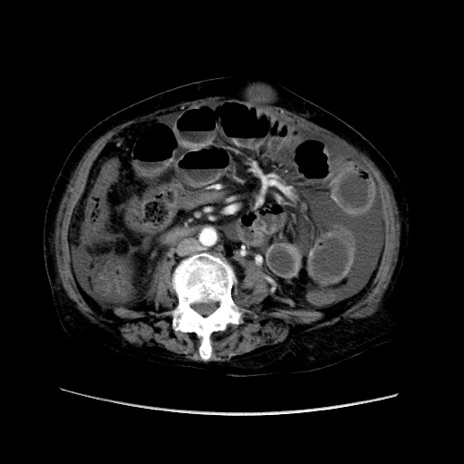

冠状断像